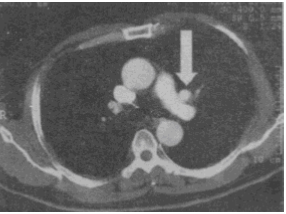

箭头所指的解剖结构是

A.左无名静脉B.左上肺动脉C.左上肺静脉D.左肺上叶尖段动脉E.左上肺叶间静脉

C